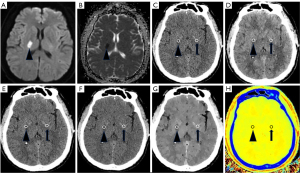

Using conventional images from the initial CT scans (see Figure 2), regions of interest (ROIs) were manually defined at the sites of ischemic lesions and the corresponding normal brain on the opposite side, with one ROI assigned to each site.

Figure 5 illustrates a clinical case of a patient with AIS, providing a comparison between traditional images and spectral images.